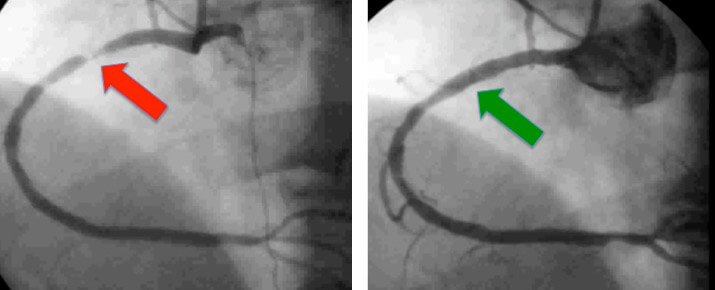

Example of coronary angiogram of a 55 year old gentleman with chest pain. Image on the left shows the right coronary artery with a severe narrowing (red arrow). Image on the right was taken after angioplasty and stenting showing resolution of the narrowing.

It is an invasive test performed in hospital to look for narrowings or blockages in the blood vessels that supply the heart. If a significant narrowing or blockage is found that appears suitable, your cardiologist may proceed immediately to perform angioplasty and stenting. Your cardiologist will discuss this possibility with you prior to the procedure. Angioplasty and stenting refers to the procedure whereby the narrowing in the blood vessel is dilated and a stent is deployed to keep the vessel patent.

Should you have significant coronary artery disease on angiogram that is amenable to angioplasty, your cardiologist may decide to proceed. Using the same sheath used for your angiogram, a specialized catheter or tube will be used to engage the relevant artery. A fine wire will then be advanced into the artery across the narrowing. This wire will be used to guide a small balloon to the site of the narrowing. The balloon is expanded to dilate the narrowing. A stent, which is a small alloy mesh in the shape of a cylinder, is usually placed at the site of the narrowing to prevent re-narrowing at this site. The balloon is then removed from the body.